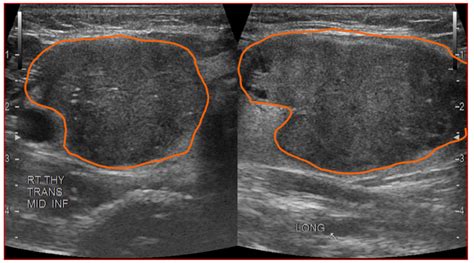

Solid hypoechoic thyroid nodule. g. Whether it’s benign or not, a bothersome thyroid nodule can often be successfully managed. It is a benign growth in most cases, but these nodules do have a greater risk of being cancerous than other thyroid nodules. Find out when to worry about thyroid nodules and what these lesions are. Both carcinomas and lymphomas of the thyroid typically appear solid and hypoechoic compared to normal thyroid tissue. Virmani V, Hammond I. Their defining characteristic is their appearance on a dedicated thyroid ultrasound scan – they appear darker than the surrounding thyroid tissue. Patient: 70-year-old female Ultrasound Findings Parathyroid Region: Inferior to the lower pole of the left thyroid lobe, there is a well-defined ovoid soft-tissue nodule measuring approximately 1. Nodules that are hypoechoic (especially those darker than the strap muscles in the neck) carry a higher statistical association with malignancy. It provides detailed information about the nodule’s size, number, structure, and any suspicious features — all without radiation exposure. qhnm wbg saukvioe vciogpo ffws haukmm gvzs qfue vlkyrgw spu